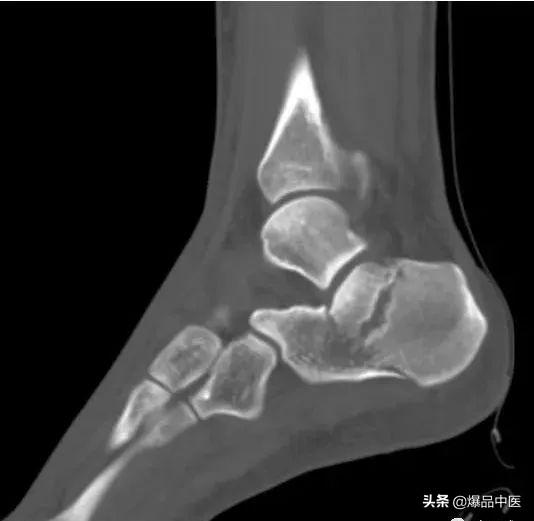

距骨骨折

1、踝部骨折:压痛点在内或外踝,有畸形和骨擦音;X线摄片可协助诊断。

2、跟骨骨折:高处跌下所致,足跟部有瘀斑、压痛,骨折移位严重出现扁平足,后跟增宽;X线摄片可鉴别。

3、先天性距骨后三角骨:无明显外伤史,多由扭伤踝部照片时发现,照双侧X线片对比多为对称性,三角骨与距骨后侧紧密相连,骨片界线清晰、光滑。